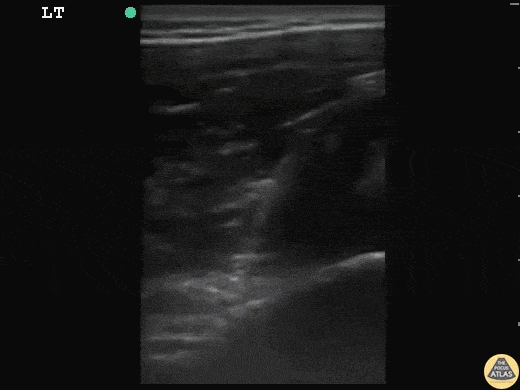

17 y/o basketball player with acute onset left shoulder pain after throwing a basketball across the court. "Feels like my arm is out of the socket." The patient was relocated with simple traction in less then 2 minutes. No x-rays were required. The head of humerus is dislocated posterior to the glenoid. After relocation it is flush with glenoid as seen. You can appreciate the musculature and rotator cuff throughout both images. Dr. Sathya Subramaniam, Pediatric EM Fellow - Kings County/SUNY Downstate